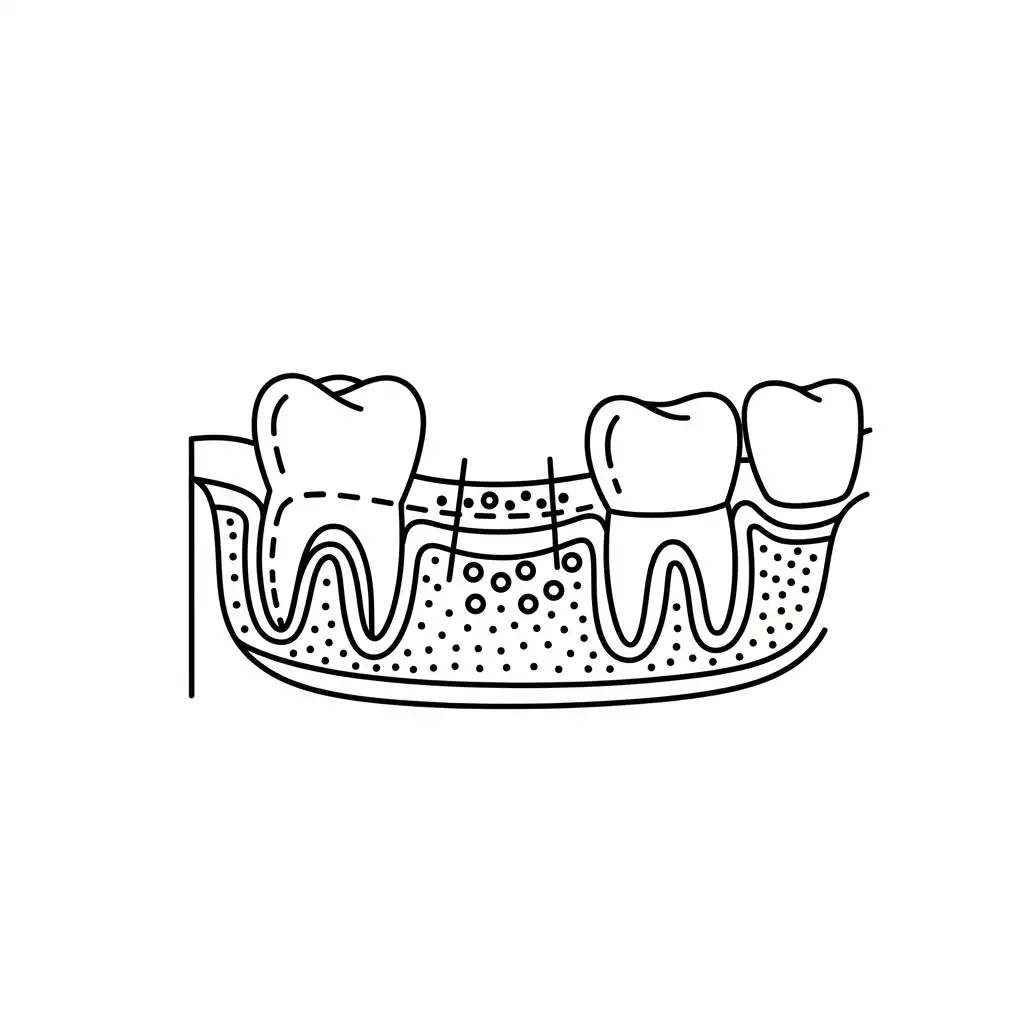

Root Canal

Save infected or decayed teeth from extraction with advanced root canal therapies.